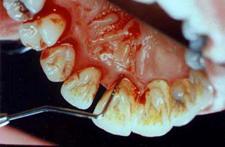

Gingivite

sângerare la periaj/sondare

gingie de culoare rosie, tumefiata, neteda, lucioasa, sensibila la palpare

halena

pungi parodontale false

ANUG

elefantiazis gingival

Parodontite usoare

sângerare gingivala mai pronuntata

gingia începe sa se detaseze fata de dinte

pungi parodontale de 3-4 mm

demineralizare osoasa halistereza

Parodontite moderate

dintii par alungiti datorita retractiei gingivale

pot apare abcese parodontale

mobilitate dentara si diastemizare patologica

pungi parodontale de 4-6 mm

resorbtie osoasa

Parodontite severe

mobilitate dentara accentuata pâna la avulsia dintilor

migrari patologice

halena constanta

hiperestezie dentinara datorata denudarii radacinii

pungi parodontale > de 6 mm

resorbtie osoasa accentuata